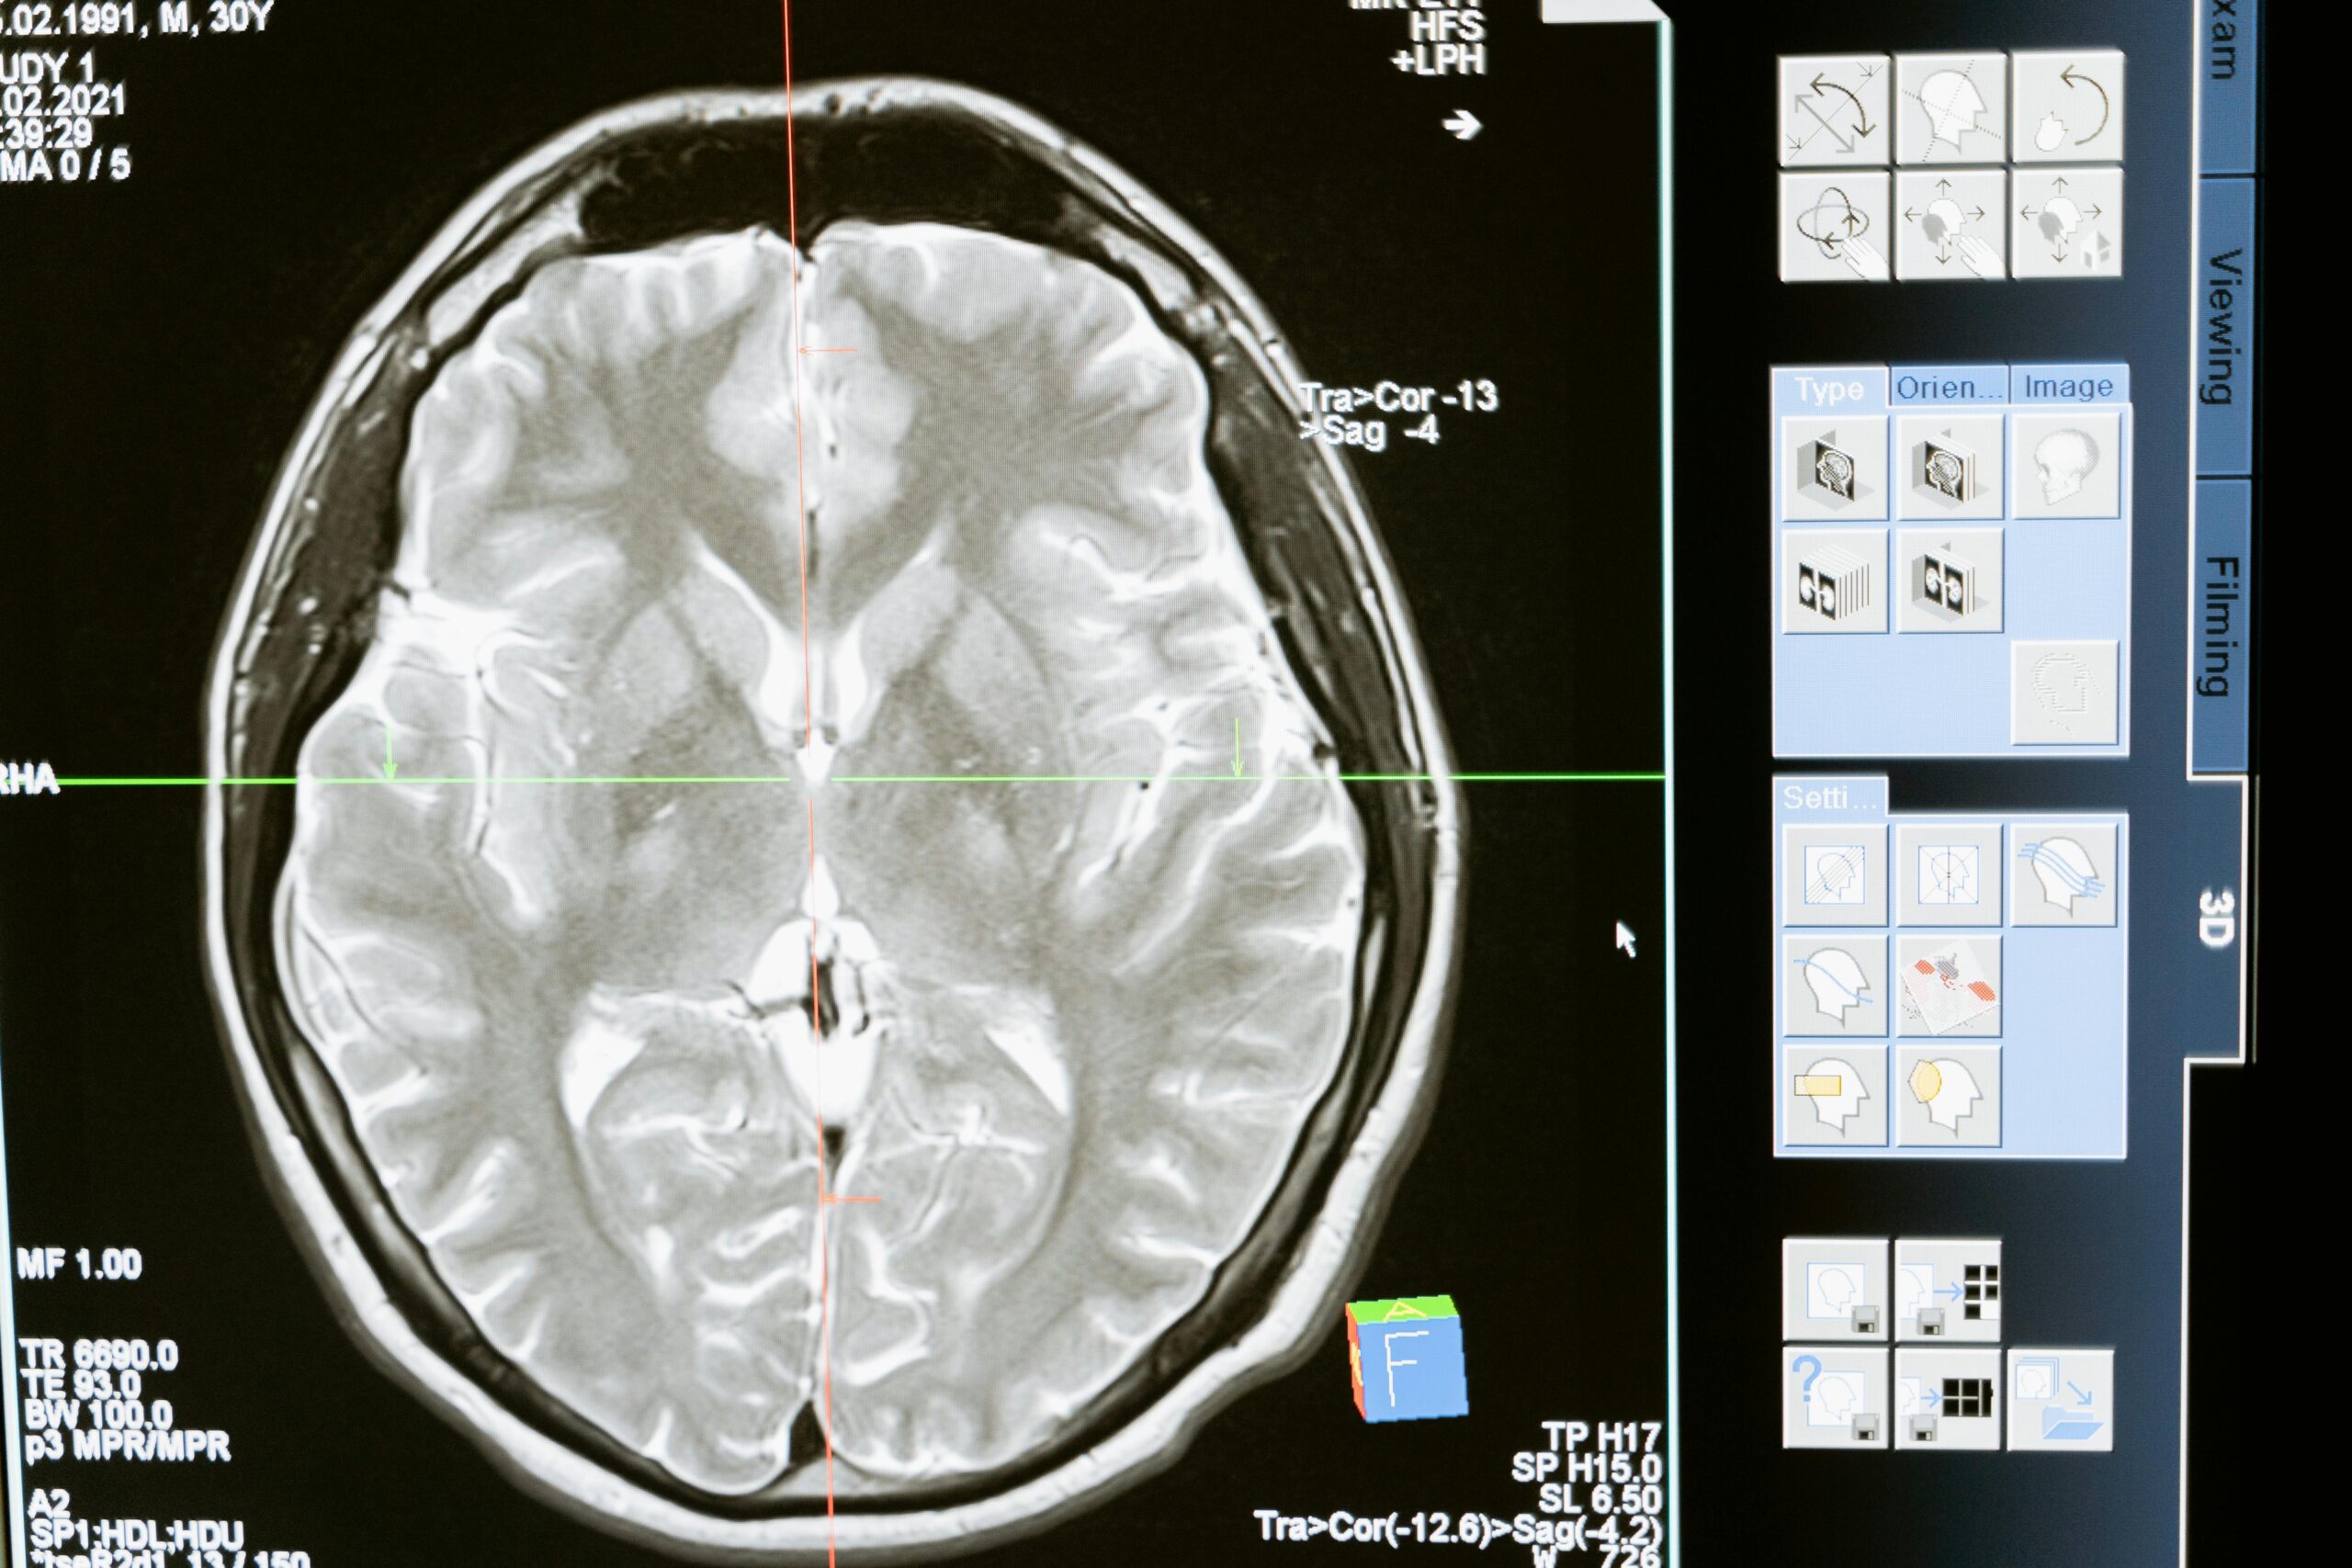

Diagnosis of Encephalitis

Timely and accurate diagnosis of encephalitis is essential for initiating treatment. Common diagnostic methods include:

- Physical and Neurological Exam: Checking reflexes, sensory function, and mental status to assess neurological impact.

- Imaging Tests: MRI or CT scans can help identify areas of inflammation or brain swelling.

- Lumbar Puncture: A spinal tap may be used to collect cerebrospinal fluid to detect signs of infection or inflammation.

- Blood and Urine Tests: These tests help identify infectious agents or abnormal immune responses.

- Electroencephalogram (EEG): Used to monitor brain activity, especially in cases where seizures are present.